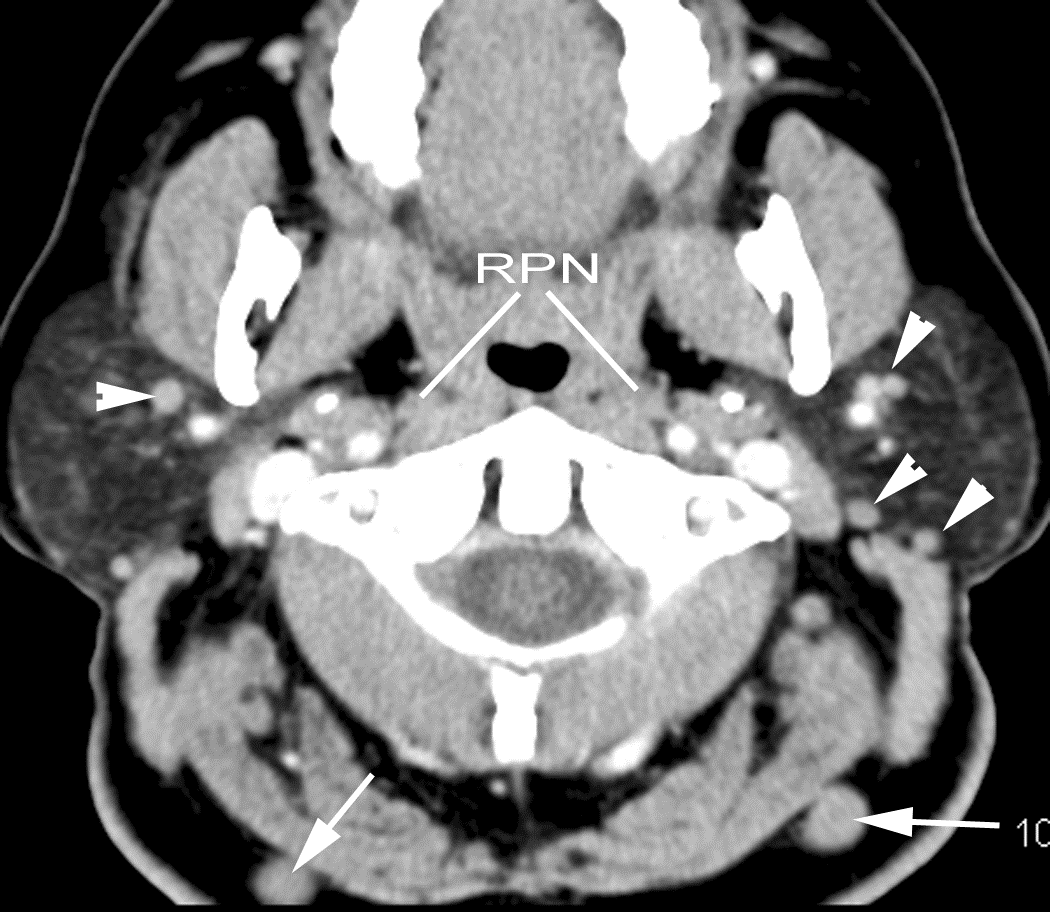

The other cervical (Levels 2-6), supraclavicular and/or retropharyngeal lymph nodes are abnormal by imaging criteria.

The submandibular (Level 1) lymph nodes are abnormal by imaging criteria.

There is evidence of thrombus, thrombophlebitis or other occlusive or inflammatory process of the jugular vein or smaller venous tributaries.